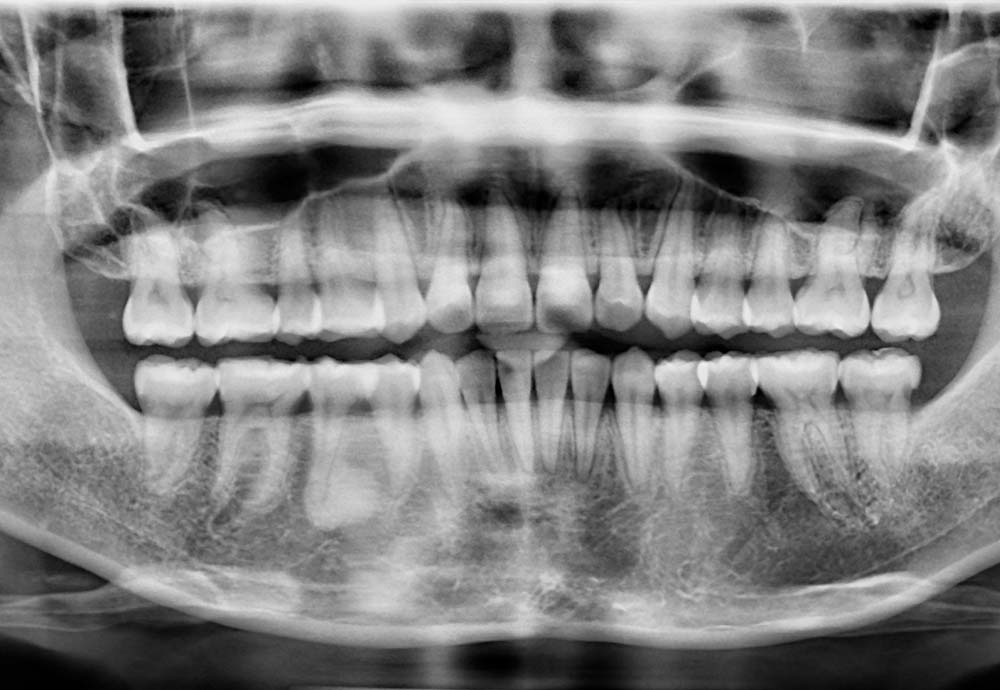

Wisdom teeth may need to be removed if they are impacted, causing pain, swelling, infection, or damage to nearby teeth.

Other reasons include preventing future dental problems such as decay, gum disease, cysts, or crowding of your existing teeth.